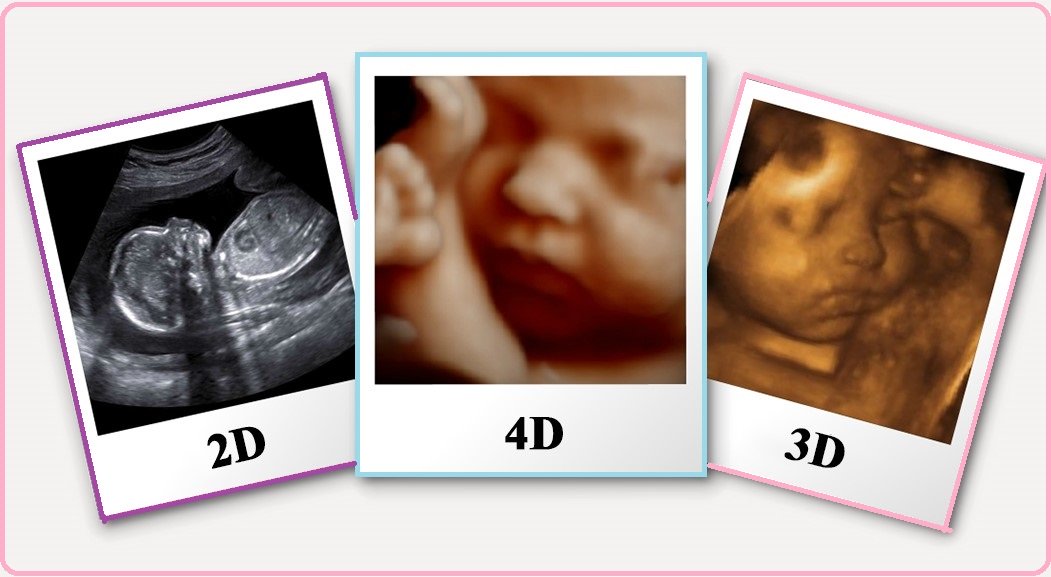

These are usually the 2D black and white scan images you are probably used to seeing in the hospital. This is because at this early stage baby isn’t yet developed enough to see in more detail. The same technology (ultrasound machine and probe) is used later in your pregnancy but is capable of showing you much more detail once your baby is sufficiently developed, usually this is possible from around 16 weeks but best images are taken around 27 weeks. These are the high detail 3D pictures that have a golden look and feel to them.

Image quality then drops off around 36 weeks because although baby is developing further there is less space for baby and fluid to help capture those pictures. 4D (sometimes referred to as ‘live’) is the same 2D or 3D image but a video capture of that examination that you can watch back at a later date. Our packages are available with scan only, scan plus picture images or scan plus picture images plus 4D video that can all be digitally downloaded directly to your mobile device.